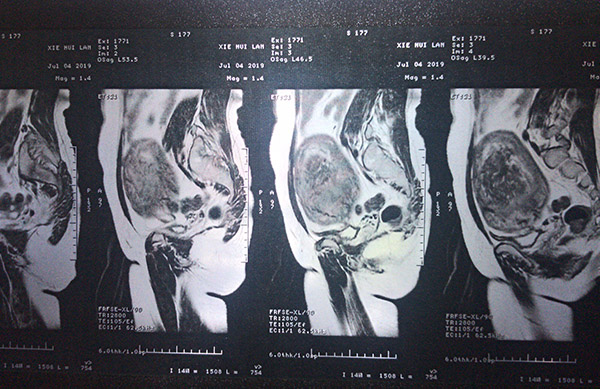

腔鏡下探查謝阿姨的子宮影像

磁共振檢查情況

謝阿姨入院后,做了婦科檢查顯示:子宮增大如孕5月余,質(zhì)硬,活動(dòng)度欠佳。王主任詳細(xì)了解患者病史,并完善相關(guān)輔助檢查。B超提示子宮增大約113*106*110mm,肌瘤約98*89*102mm大小,手術(shù)指征明確,經(jīng)過(guò)科室術(shù)前討論評(píng)估,決定為謝阿姨做腹腔鏡子宮全切+雙側(cè)輸卵管切除術(shù)。